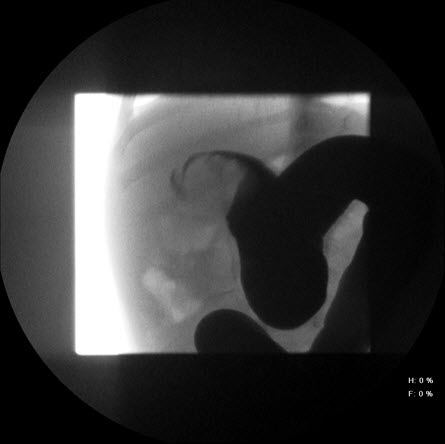

Intussuscepção: local de intussuscepção conforme revelado pela radiografia abdominal, que mostra o menisco

Do acervo de Dr. David J. Hackam